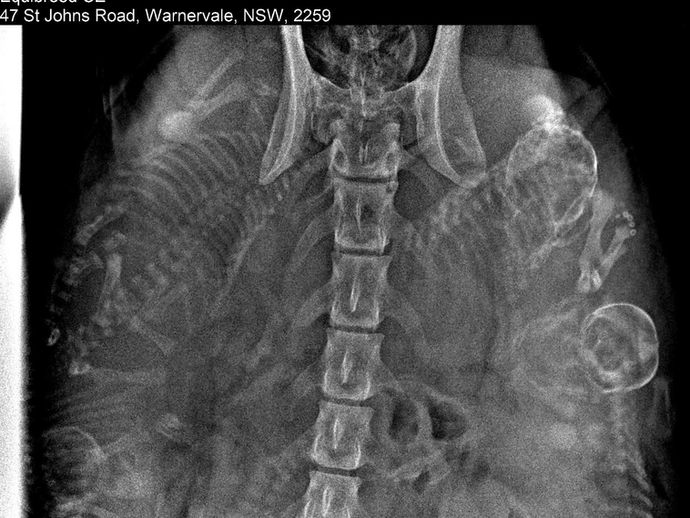

carolinekjandersonNov 14, 20221 min readSalla’s Puppy X-raysSalla had her pregnancy X-rays done on 04 November 2022 by Dr Peter Tazawa at Sires on Ice in Calga. Consistent with his estimate at...